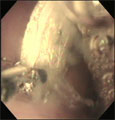

内視鏡処置中

把持鉗子で1円玉を摘出

経過:一般状態良好。レントゲンにてコインを確認し催吐したが吐き出さなかった。24時間絶食後、全身麻酔下にて、胃内視鏡検査を行った。胃内に1円玉を確認し、把持鉗子にて摘出した。処置時間は21分だった。

コメント:1円玉が多量の粘液にからまっていてすこし苦戦しましたがしっかり摘出しました。